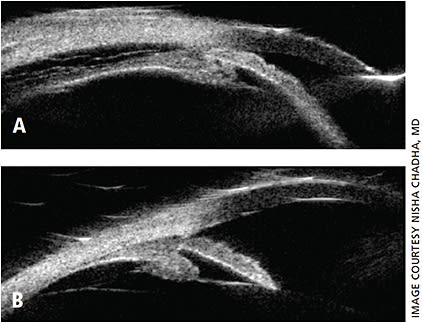

Since TiACG was first reported by Banta et al. in 2001, many other cases have appeared in ophthalmology literature.2-6 TiACG usually presents with sudden, bilateral decrease in vision due to myopic shift from topiramate-induced ciliary body edema. Clinical exam demonstrates shallow anterior chamber from forward rotation of the lens-iris diaphragm, closed angle on gonioscopy and choroidal effusions (Figures 1 and 2).